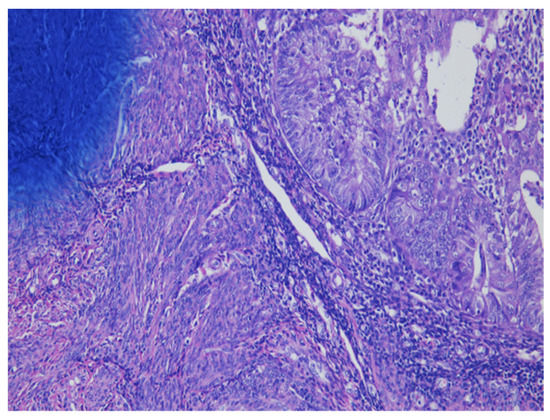

As shown in Figure 1 of EC at the uterine cornus, negative MI was found with an intact thin rim of stroma between the tumor–myometrium junction on the left side and with positive MI featuring an absence of stroma between the junction on the right side. A further higher power scope of the left side and right side of Figure 1 is shown in Figure 2 and Figure 3, respectively. Figure 2 demonstrated a thin rim of endometrial stroma between the tumor-myometrium junction (dark blue area: dark blue nuclei of stromal cells), and Figure 3 revealed the superficial early MI. MI determined by histopathology was the gold standard for comparison.

Figure 3.

The absence of stromal cells in between tumor and myometrium hints the superficial myometrial invasion (200× magnification).